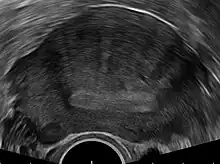

Transvaginal ultrasonography

Transvaginal ultrasonography is a cheap and readily available imaging test that is typically used early during the evaluation of gynecologic symptoms.[24] Ultrasound imaging, like MRI, does not use radiation and is safe for examination of the pelvis and female reproductive organs.[25] Overall, it is estimated that transvaginal ultrasonography has a sensitivity of 79% and specificity of 85% for the detection of adenomyosis.[11]

Common transvaginal ultrasound findings are defined by the European MUSA group in 2015 [26] and are defined in 2022 by the MUSA group.[27] The ultrasound characteristics can be divided in direct and indirect features.

Direct features:

- myometrial cysts - pockets of fluid within the smooth muscle of the uterus

- Hyperechogenic islands - usually white endometrium islands within the myometrium

- Echogenenic subendometrial lines and buds - usually white lines and knobs attached to the endometrium, prtruding into the myometrium.

Indirect features:

- Globular, enlarged, and/or asymmetric uterus

- Fan shaped shadowing - differentiating from fibroids with linear shadowing

- Anterior/posterior wall asymmetry

- Translational vascularity - diffuse spread of small vessels within the myometrium

- Irregular or interrupted junctional zone - the borderline between the endometrium and myometrium

The power Doppler or Doppler ultrasonography function can be used during transvaginal ultrasonography to help differentiate adenomyomas from uterine fibroids.[24][28][29] This is because uterine fibroids typically have blood vessels circling the fibroid's capsule. In contrast, adenomyomas are characterized by widespread blood vessels within the lesion.[24] Doppler ultrasonography also serves to differentiate the static fluid within myometrial cysts from flowing blood within vessels.[24]

The junction zone (JZ), or a small distinct hormone-dependent region at the endometrial-myometrial interface, may be assessed by three-dimensional transvaginal ultrasound (3D TVUS) and MRI. Features of adenomyosis are disruption, thickening, enlargement or invasion of the junctional zone.[21] There is no consensus about the actual histology of the junctional zone and a recent review showed that the ultrasound, MRI and histology all define and describe the junctional zone differently.[30]